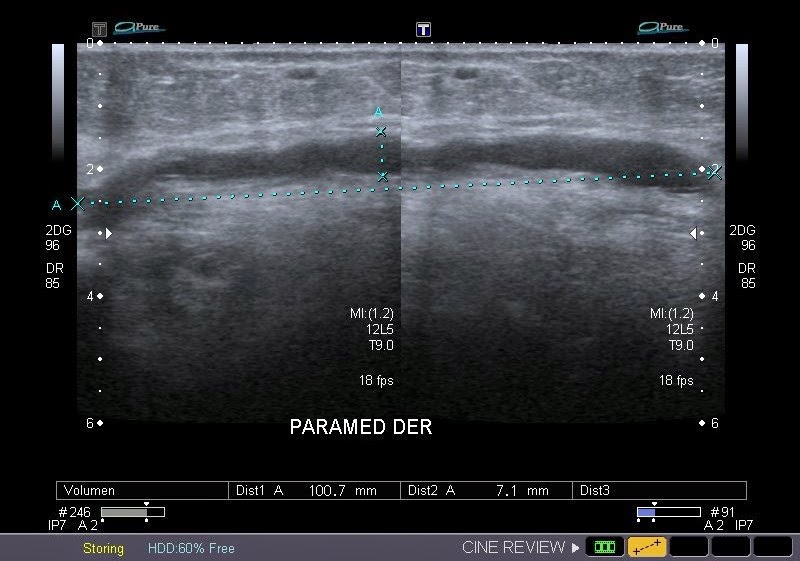

Caso Interesante #1

INGRESO

Paciente con antecedente de ALIF (Fusión lumbar intersomática anterior) 360 grados L5-S1 hace siete meses, quién presenta herida de abordaje anterior con dehiscencia de sutura, con cierre por segunda intención, quien consulta por cuadro clínico de dos días de secreción purulenta en herida quirúrgica, niega fiebre, niega otras sintomatología, refiere episodios previos similares.

EVOLUCIÓN

Paciente en POP de ALIF L5-S1 quien presento dehiscencia de la herida abdominal con ISO superficial ya tratada, sin embargo persiste con dehiscencia y desde ayer con supuración asociado a fiebre subjetiva. Se realiza eco abdominal con colección en pared sugestiva de absceso, elevación de RFA por lo cual se considera se debe hospitalizar para manejo antibiótico, drenaje de la colección, manejo médico y vigilancia neurológica.

- ¿Hallazgos Escanografia?